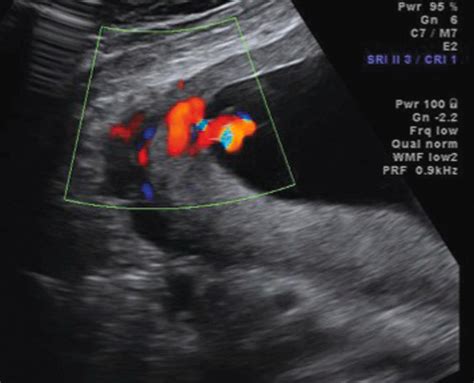

• Doppler Studies: A specific type of ultrasound that measures blood flow through the umbilical cord to ensure the placenta is functioning correctly.